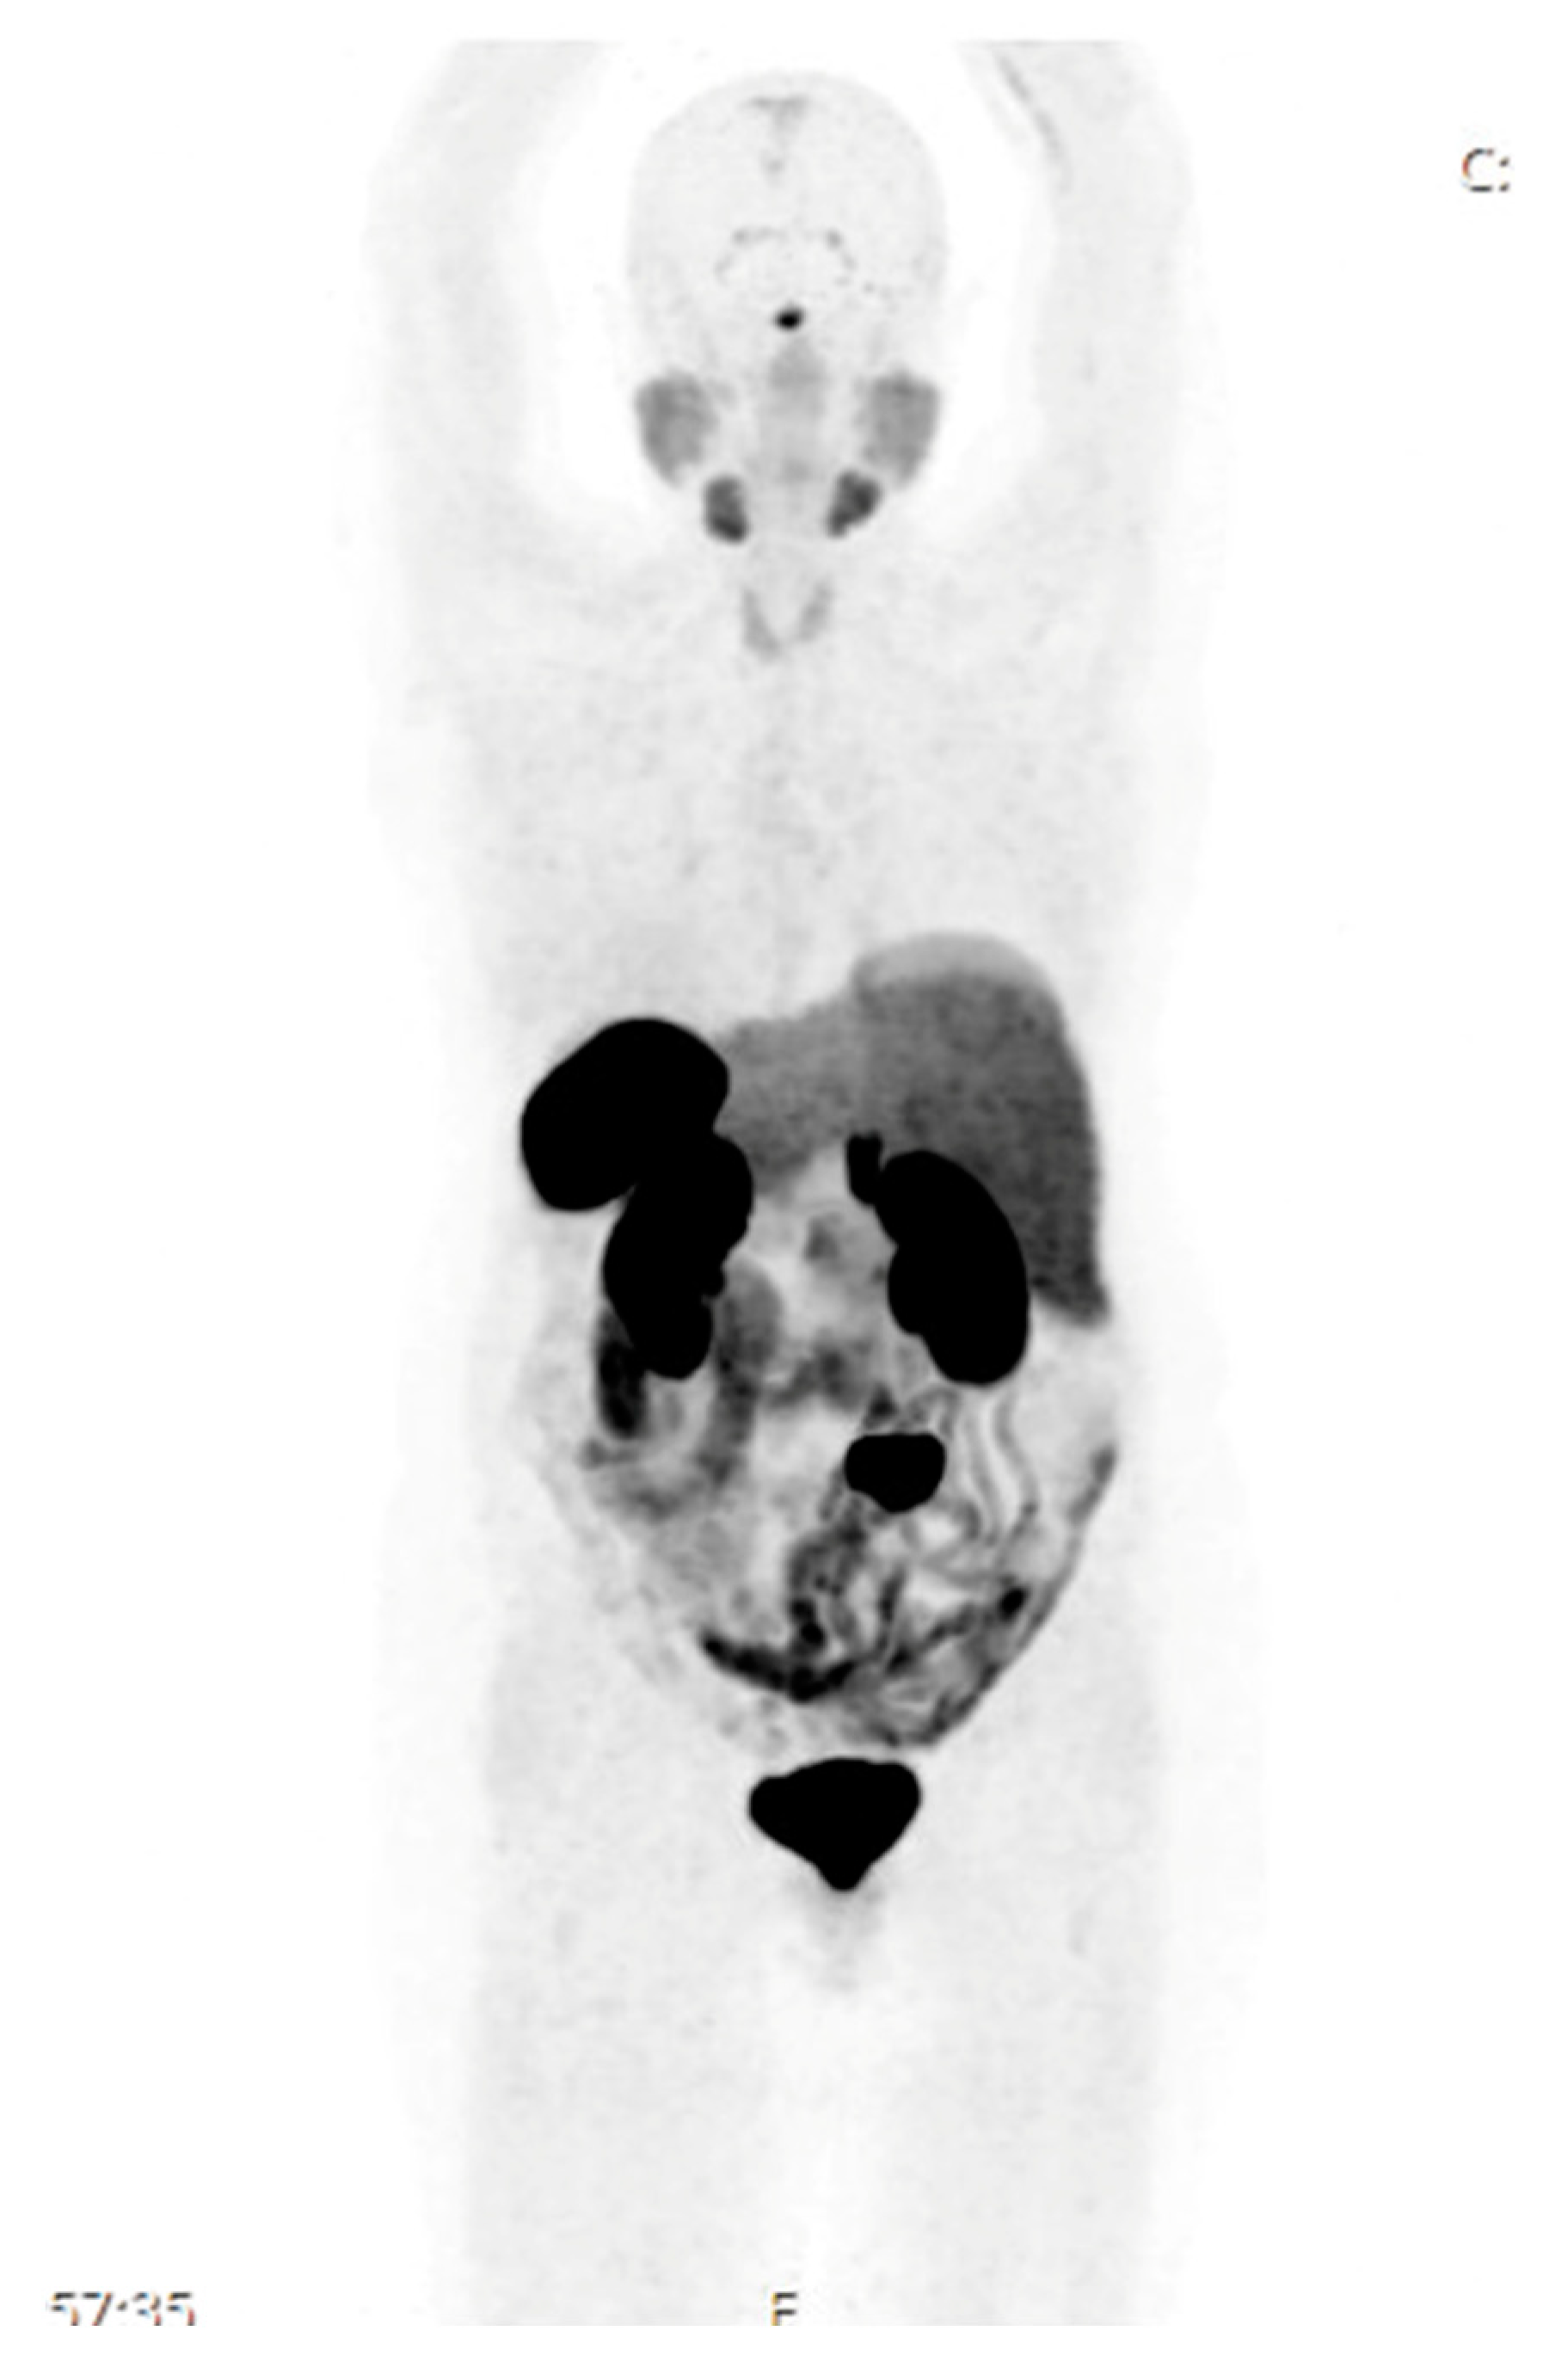

A Case of Cushing’s Syndrome from Well-Differentiated Neuroendocrine Tumors of the Small Bowel and Its Mesentery

2. Case Presentation